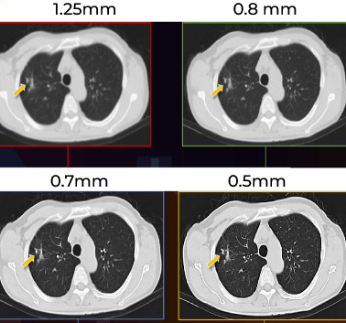

Redução de ruídos e artefatos

Imagens mais nítidas

Protocolos otimizados para diferentes qualidades de imagem